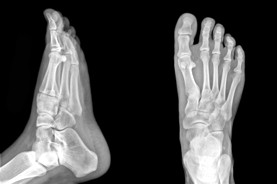

Calgary Foot Doctor & Foot Physio Therapist

The Foot Institute is an association of Calgary Doctors specializing in the medical treatment of the foot and ankle, and is one of the largest groups of foot specialists in Alberta.

The Calgary Foot Institute is dedicated to the medical and surgical treatment of the foot. Our mandate is to provide the best possible medical, surgical and preventative treatment available for our patients. We do this by providing well-trained Doctors who are committed to treat and prevent all types of foot pain, biomechanical disorders, as well as all other problems relating to the feet.

At the Calgary Foot Institute, our Doctors are trained to specifically treat problems associated with your feet or ankles. Below are several of the most common problems that we see on a day to day basis: